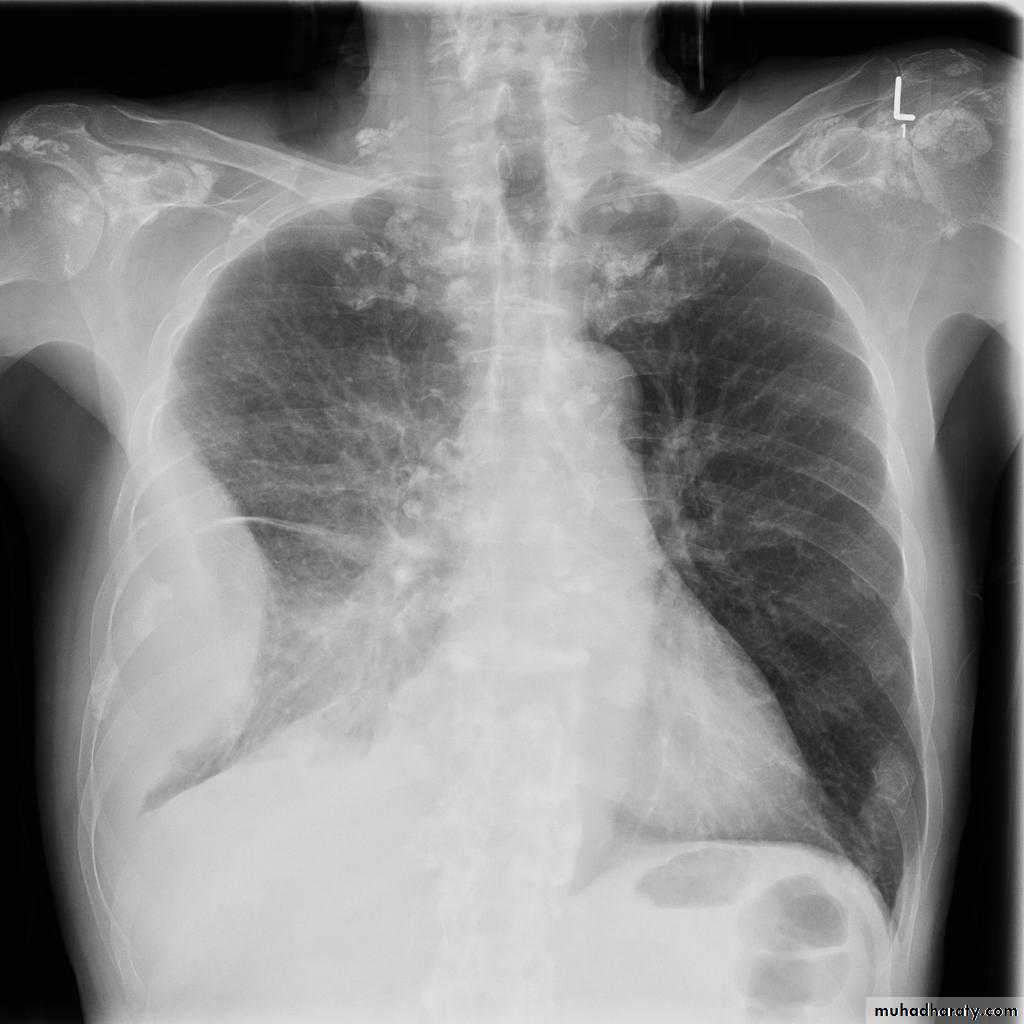

Pulmonary metastases are common and the result of metastatic spread to the lungs from a variety of tumors and can spread via blood or lymphatics.1.Cannonball metastases refer to large well circumscribed, round multiple opacities like cannonballs

2.lymphangitis carcinomatosis , is the term given to tumor spread through the lymphatics of the lung , and is most commonly seen secondary to adenocarcinoma Unfortunately up to a quarter of patients with subsequently established lymphangitic carcinomatosis have normal chest x-rays . When abnormal the most common finding is of a reticulonodular pattern, with thickening of the interlobular septae which may resemble Kerley B lines + /- pleural effusion .

3.innumerable small metastases (miliary pattern).